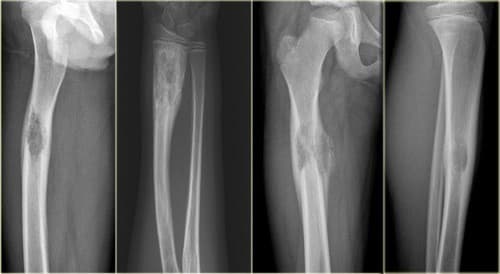

- Chụp X quang: Cho thấy hình ảnh phá hủy thân đốt sống hay xẹp lún đốt sống, hình ảnh u xương tại các vị trí nghi ngờ tổn thương.

Bệnh gặp nhiều hơn ở người trưởng thành tại các đầu xương lớn như đầu dưới xương đùi, đầu trên xương chày, xương cùng… U tế bào không lồ chiếm khoảng 5 – 10% u xương nguyên phát và gặp nhiều hơn ở nữ giới.